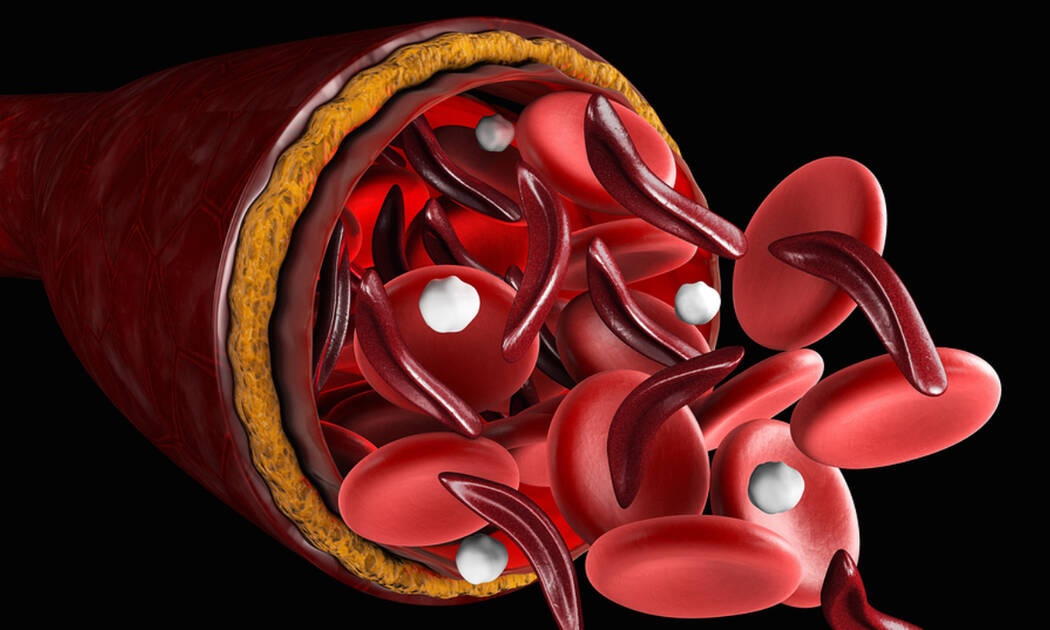

Αποθηκεύεται στους ιστούς κυρίως με την μορφή της φεριτίνης, απορροφάται από την τροφή στο λεπτό έντερο και περνά στο αίμα και στον μυελό των οστών. Εκεί χρησιμοποιείται στην παρασκευή αιμοσφαιρίνης, η οποία ενσωματώνεται στα ερυθρά αιμοσφαίρια.